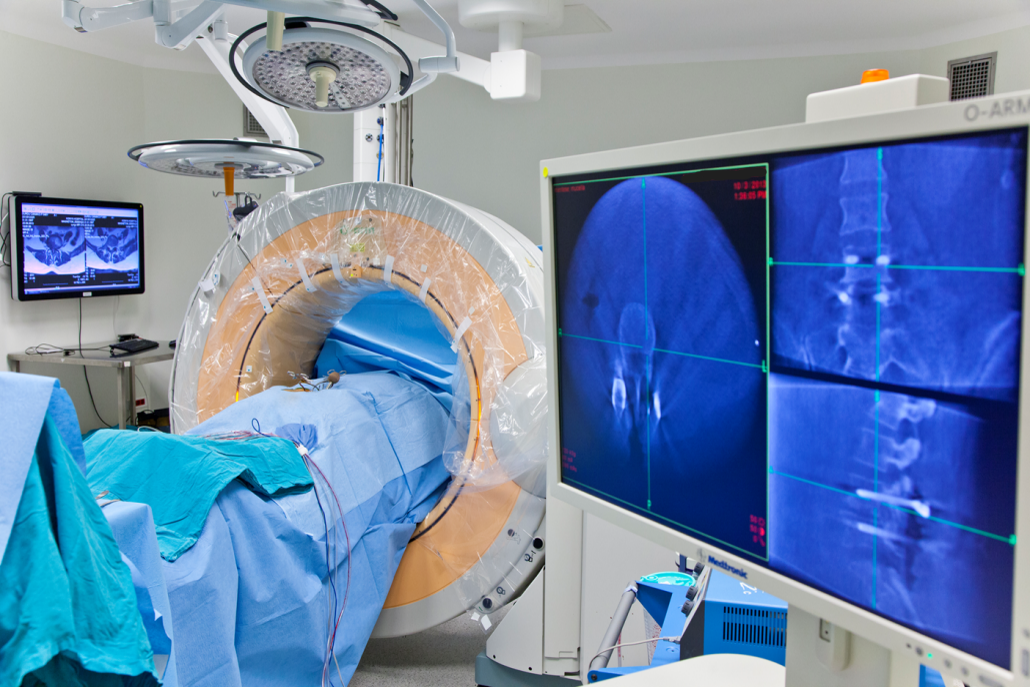

In neurosurgery, precision and accuracy are paramount. The O-Arm CT system is an advanced, intraoperative imaging tool that is revolutionizing the way complex spinal surgeries are performed. It provides real-time, high-resolution, three-dimensional imaging during surgery, enabling neurosurgeons to make precise decisions and achieve optimal outcomes for their patients. This mobile, multi-dimensional imaging system is increasingly used in the operating room (OR) for spinal surgeries and some critical neurosurgical procedures.

The O-Arm CT plays a crucial role in improving the safety and efficacy of neurosurgical procedures. Traditional imaging methods, such as preoperative CT or MRI scans, provide static images of the patient’s anatomy. However, these images can quickly become outdated once the surgery begins. The O-Arm CT, provides real-time intraoperative imaging, allowing surgeons to visualize the surgical site in three dimensions while performing the procedure.

O-Arm CT © ENI

The O-Arm CT system consists of a large, O-shaped apparatus that surrounds the patient while rotating 360 degrees to capture multiple images during surgery. These images are then processed by advanced software to create high-resolution 2D and 3D images that can be viewed by the surgical team on a computer screen.

O-Arm CT © ENI